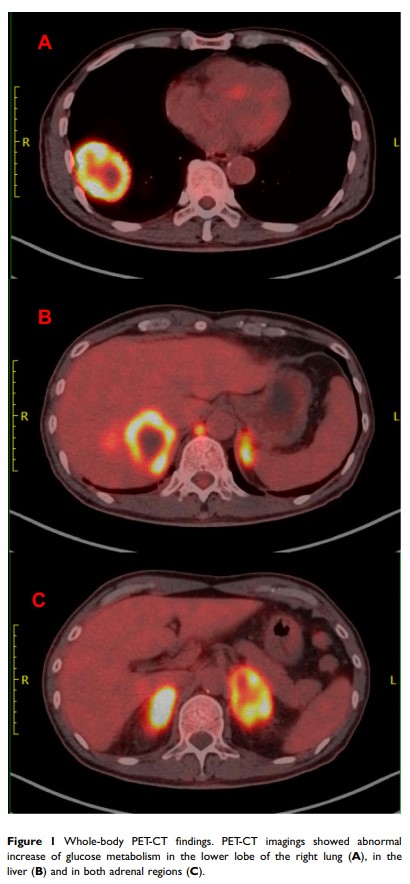

免疫治疗联合化疗作为有潜力的治疗方法治疗 EGFR 外显子 19 缺失及 MET 扩增的非小细胞肺癌患者的一例病例